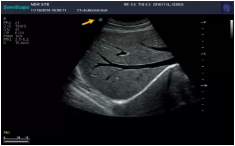

Mark點(diǎn):每一把探頭都有一個(gè)mark點(diǎn),是用于定位方向, mark點(diǎn)一側(cè)始終對(duì)應(yīng)著圖像S點(diǎn)(圖像箭頭標(biāo)識(shí))一側(cè)。

左室長(zhǎng)軸

腰椎小關(guān)節(jié)

劍下四腔

四腔心